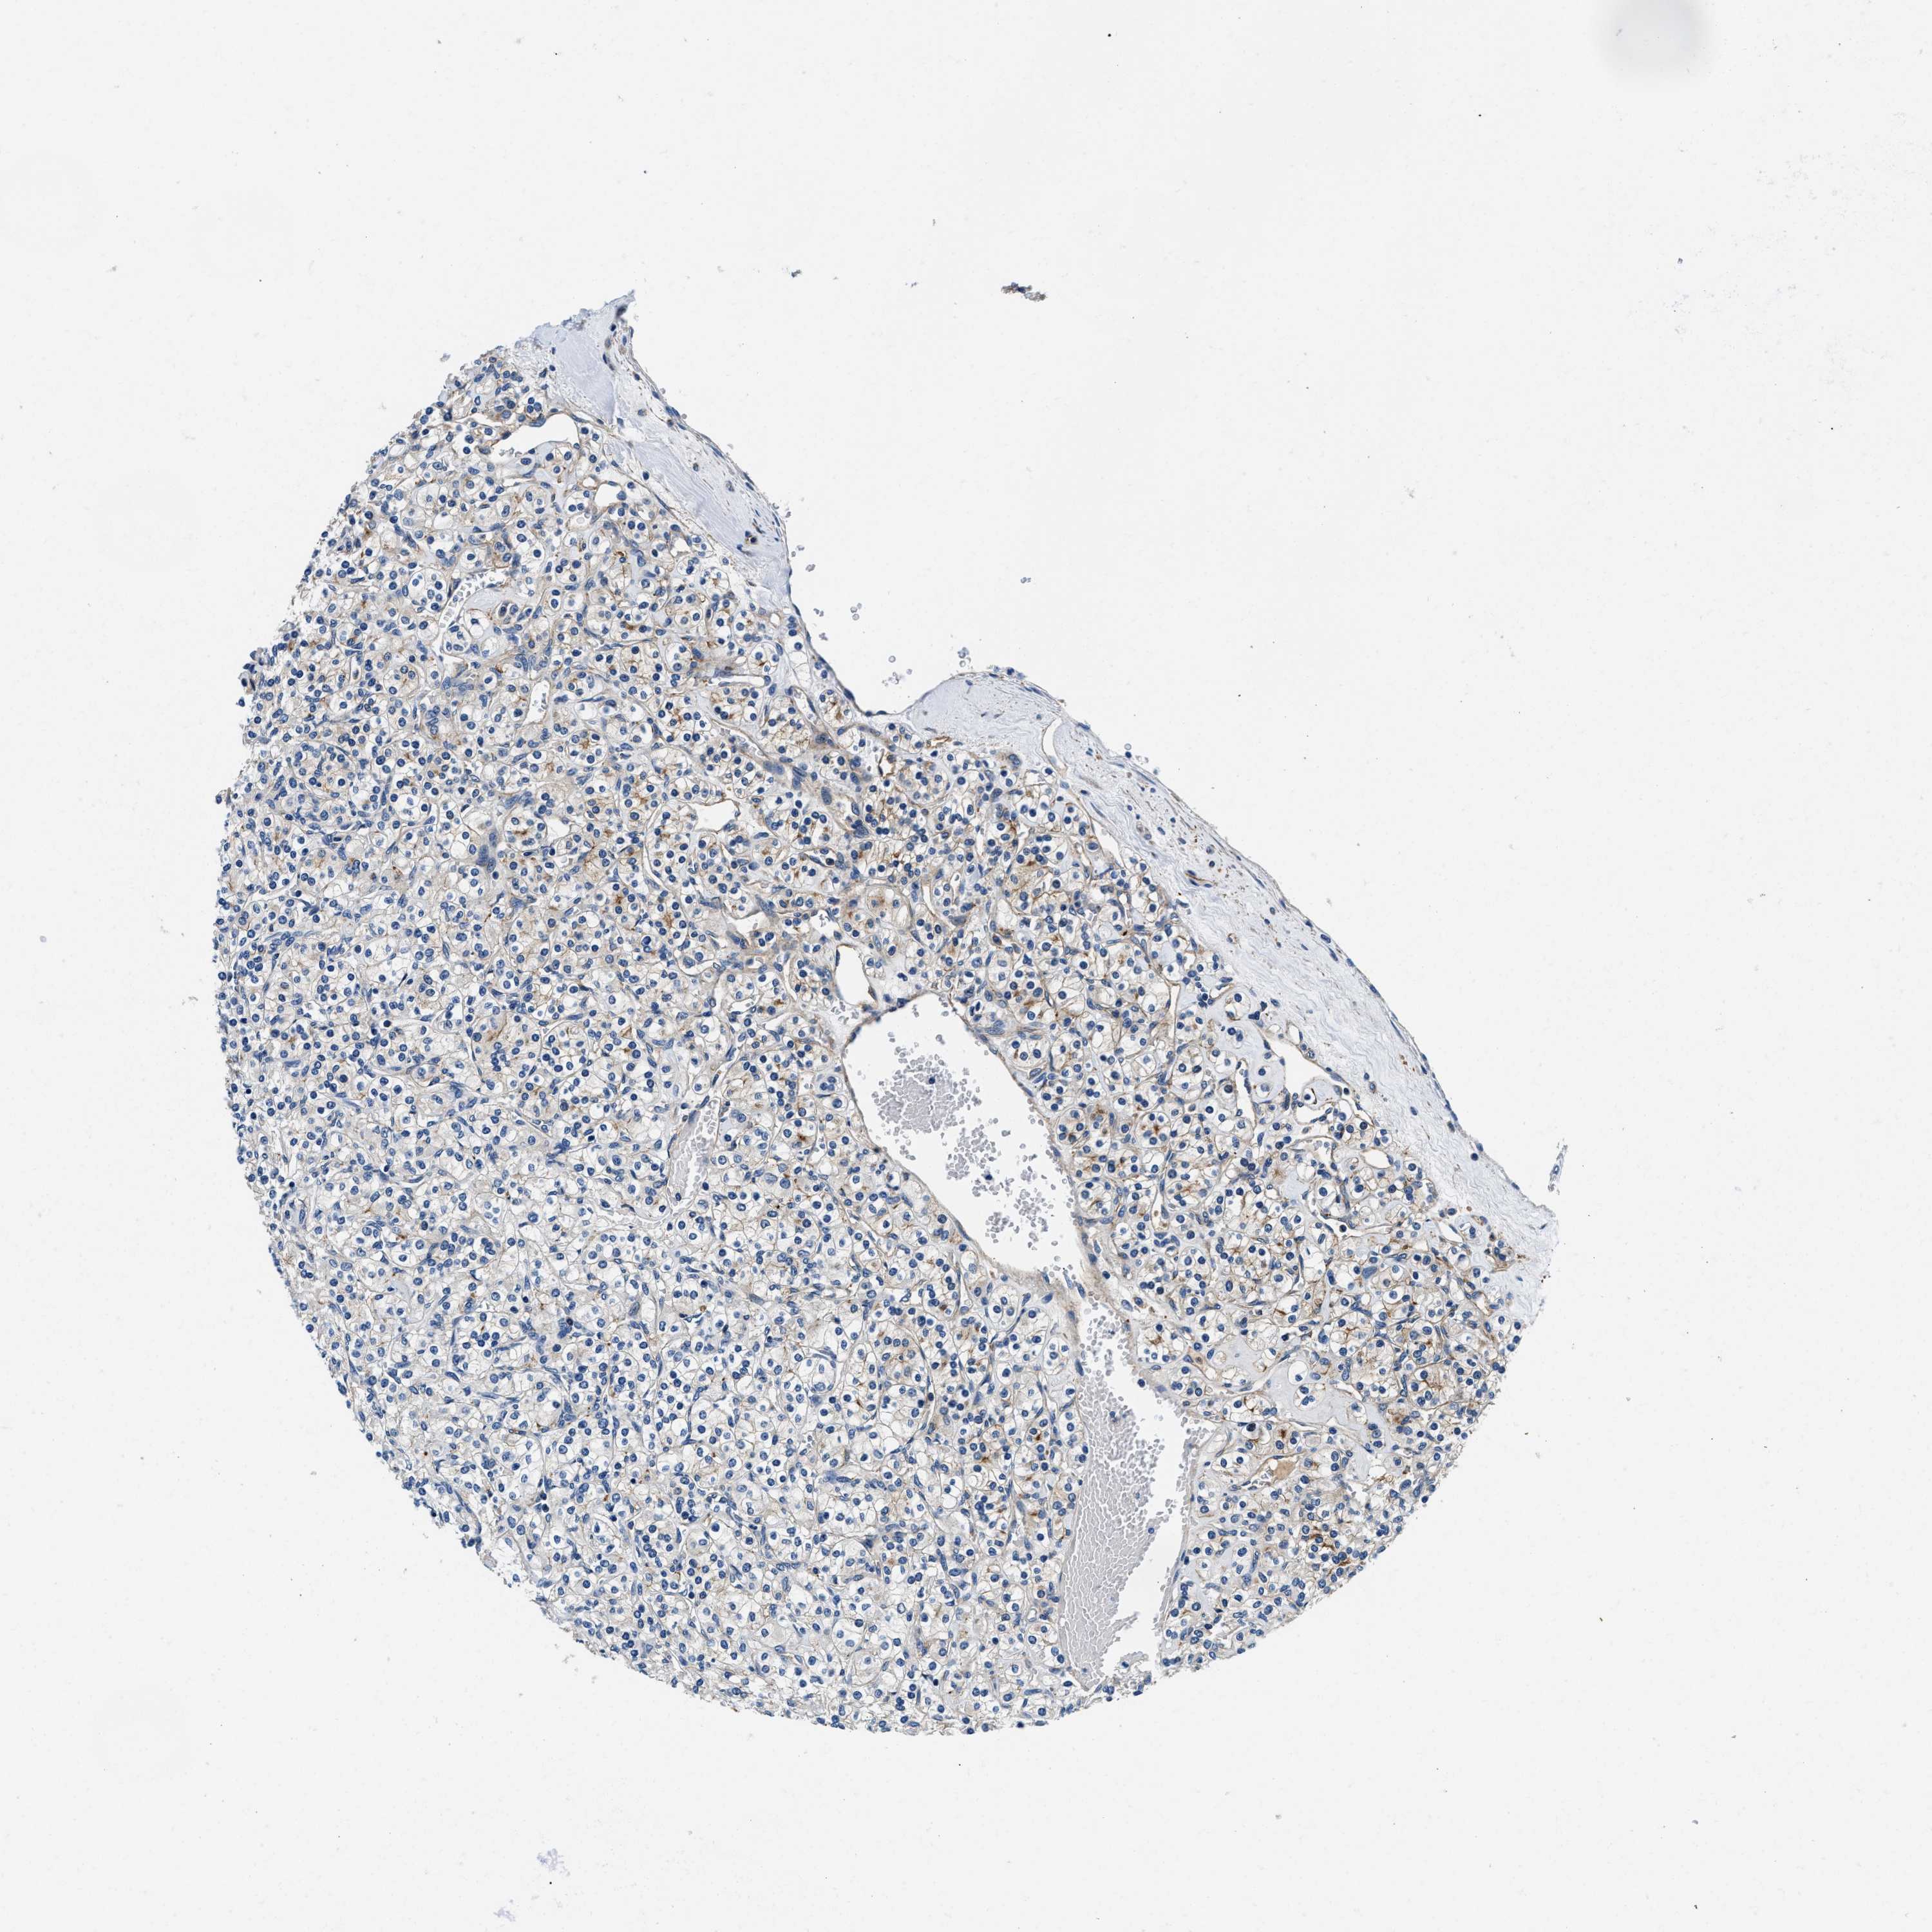

KIDNEY RENAL CLEAR CELL CARCINOMA (VALIDATION) - Interactive survival scatter ploti

The Survival Scatter plot shows the clinical status (i.e. dead or alive) for all individuals in the patient cohort, based on the same data that underlies the corresponding Kaplan-Meier plots. Patients that are alive at last time for follow-up are shown in blue and patients who have died during the study are shown in red.

ZFAND3 is not prognostic in Kidney Renal Clear Cell Carcinoma (validation)

Best expression cut offi

: 52.03

Average pTPM 62.4

Number of samples 100